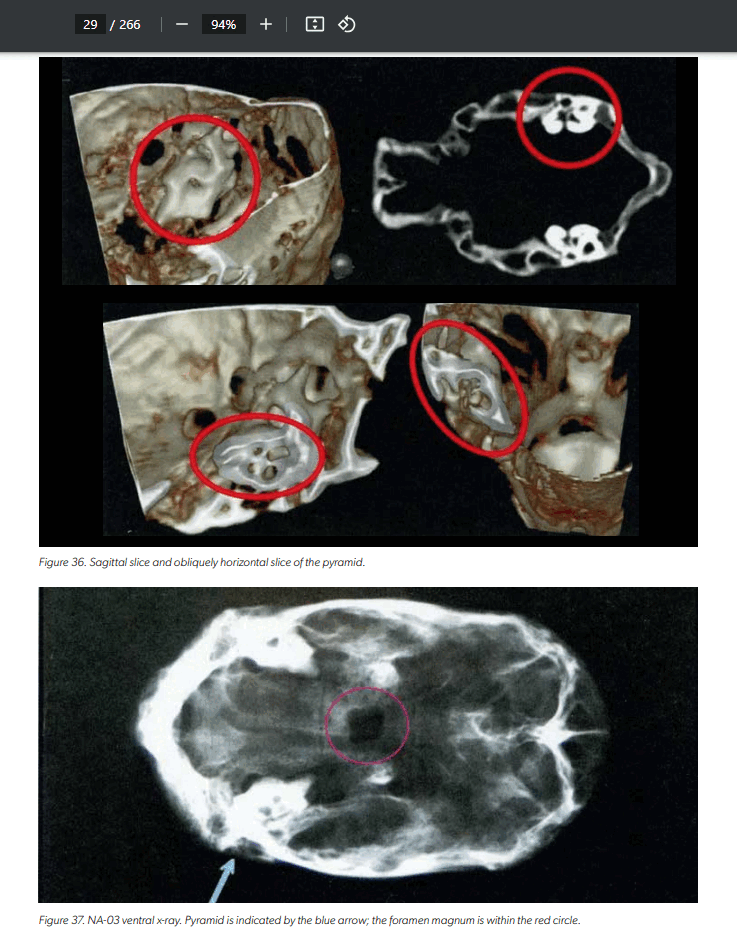

Các nhà làm phim cho biết 'xác ướp ngoài hành tinh' ba ngón kỳ lạ là có thật và chứa DNA độc nhất

Các nhà làm phim Michael Mazzola và Serena DC cho biết họ đang ghi lại bằng chứng về “xác ướp người ngoài hành tinh” giống như những xác ướp đã gây chú ý ở Peru năm ngoái.

Các nhà làm phim cho biết tia X và các xét nghiệm khác chứng minh mẫu vật của họ là hàng thật.

Serena và Mazzola cho biết một phân tích cho thấy số liệu của họ có 30% DNA “không xác định” .

Đây không phải là một trò lừa bịp về việc khám nghiệm tử thi người ngoài hành tinh ở Nazca